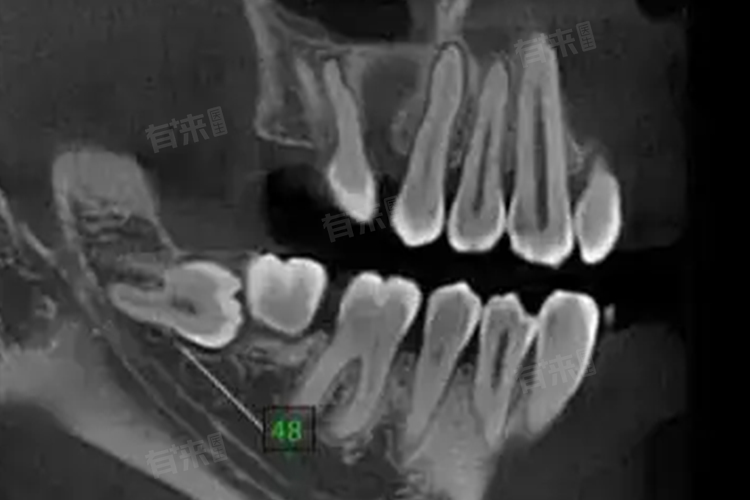

- 如果智齿横着长,但未影响邻牙,且无龋齿、炎症等不适症状,可以暂时不进行治疗,但需定期观察,建议每半年到一年进行一次口腔检查,通过X线片监测智齿的生长情况。

- 消炎后,如果智齿仍然横着长且对口腔健康构成威胁,建议拔除。拔牙前,医生会进行全面的检查,评估智齿的位置与神经管的关系,制定详细的拔牙方案。拔牙后,需按照医生的建议进行护理,如咬棉球止血、避免刷牙漱口、保持口腔清洁等。